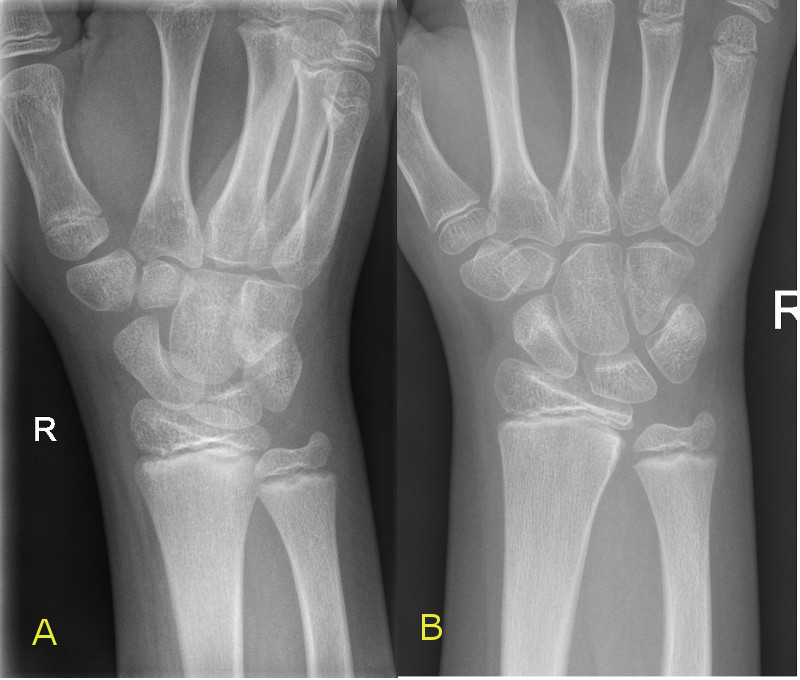

Left image: Transverse fracture of distal radius with 15 degree dorsal angulation

Right image: Completely displaced fracture of distal radius and ulna